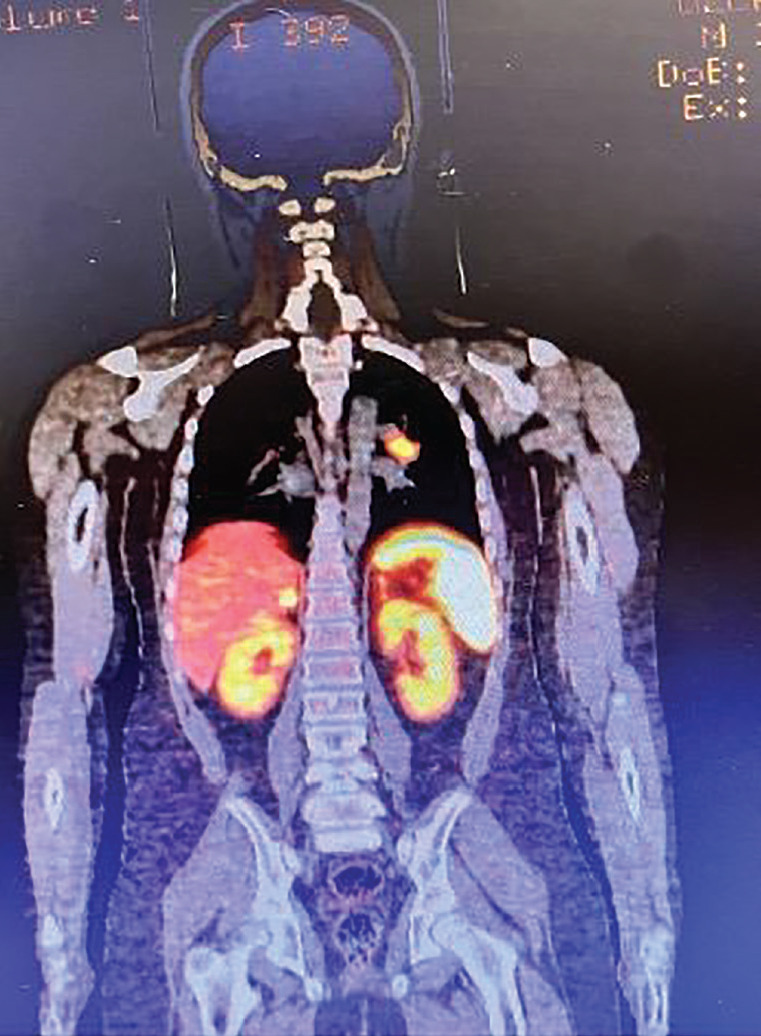

在此,我们报告一名青春期男孩被诊断为非典型支气管类癌引起的异位促肾上腺皮质激素综合征(EAS)。对患者进行了多学科评估:他进行了手术,随后接受了化疗和放疗。病人仍在我们的随访中。迄今为止,在13例病例报告和文献综述中报道了18例儿童和青少年支气管类癌EAS患者。支气管类癌引起的异位ACTH综合征在儿童和青少年中非常罕见。应立即开始仔细的诊断评估和快速治疗。尽管支气管类癌可能完全缓解,但非典型类癌具有更大的侵袭性。多学科方法和后续行动将提高生活质量和生存率。

We report an adolescent boy diagnosed with ectopic adrenocorticotropin hormone syndrome (EAS) due to an atypical bronchial carcinoid. The patient was managed by a multidisciplinary team. He underwent surgery and subsequent chemotherapy and radiotherapy treatments. The patient is still under our follow-up. At the time of writing, eighteen pediatric and adolescent patients with EAS because of bronchial carcinoid tumors have been reported. EAS due to bronchial carcinoids is very rare in children and adolescents. Careful diagnostic evaluation and rapid treatment should be started immediately. Although complete remission is possible, atypical carcinoids have a more aggressive nature. A multidisciplinary approach and follow-up is recommended in terms of quality of life and survival.